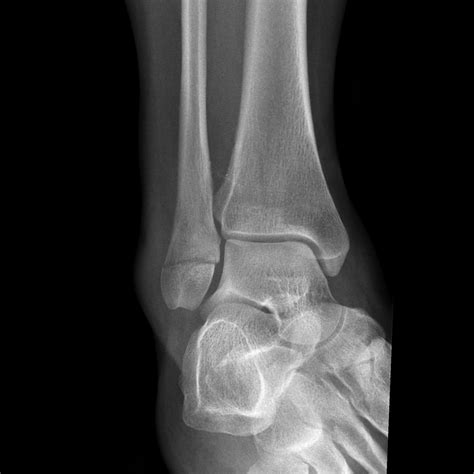

Diagnosing a Lateral Malleolus Fracture

Diagnosing a Lateral Malleolus Fracture involves a combination of physical examination and imaging tests. The diagnostic process typically includes:

• Physical Examination: A healthcare provider will assess the ankle for swelling, tenderness, and deformity. They may also check the range of motion and stability of the joint.

• Imaging Tests:

• X-rays: Standard X-rays can reveal the presence and extent of the fracture. Multiple views may be taken to get a comprehensive picture.